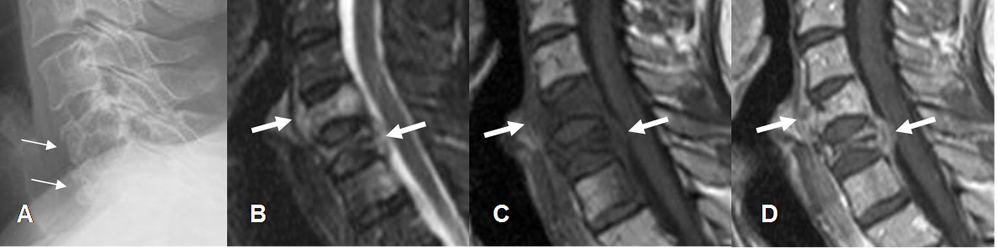

Fig 220. Fractura maligna.

A: Rx lateral. Pérdida de altura e irregularidad de los cuerpos vertebrales, con aumento del espacio retroesofágico.

B: RM sagital en STIR, C: RM sagital en T1 simple y D: RM sagital en TI con contraste. Pérdida de altura en los 2 cuerpos superiores y alteración en la señal del inferior, siendo hipointensos en T1 e hiperintensos en STIR. Los cuerpos con pérdida de altura presentan bordes convexos y masa de tejidos blandos anterior y posterior, que realzan con el contraste. (Flecha gruesa). Los cambios corresponden a enfermedad metastásica de pulmón.